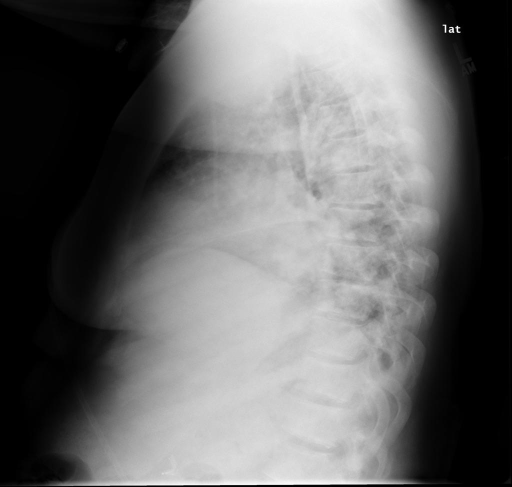

In conventional chest X-Ray exams, the erect patient is positioned between an X-Ray tube and a detector. The collected data by the detector is then used to create a comprehensive image. The main distinctions in positioning (such as anteroposterior (AP) and posteroanterior (PA), both of which we refer to a Frontal, or lateral (L)), are related to which view enables the most insight.

We compare our projected X-Rays with samples from the OpenI dataset for frontal and lateral views in Figure 5. The differences in the frontal view are due to the different positioning of the shoulder girdle. In the X-Rays, the arms are usually placed alongside the body, while in the projected images, the arms are raised due to the nature of the CT scan. In the lateral view, the X-Rays show a more comprehensive range of orientation and pose. However, the projected images, typically taken while the patient is lying down, result in similar poses between the different images. This leads to visual differences between images of female patients in both frontal and lateral views, such as the third column and second row of real X-Ray images and the first column and second row of projected images.